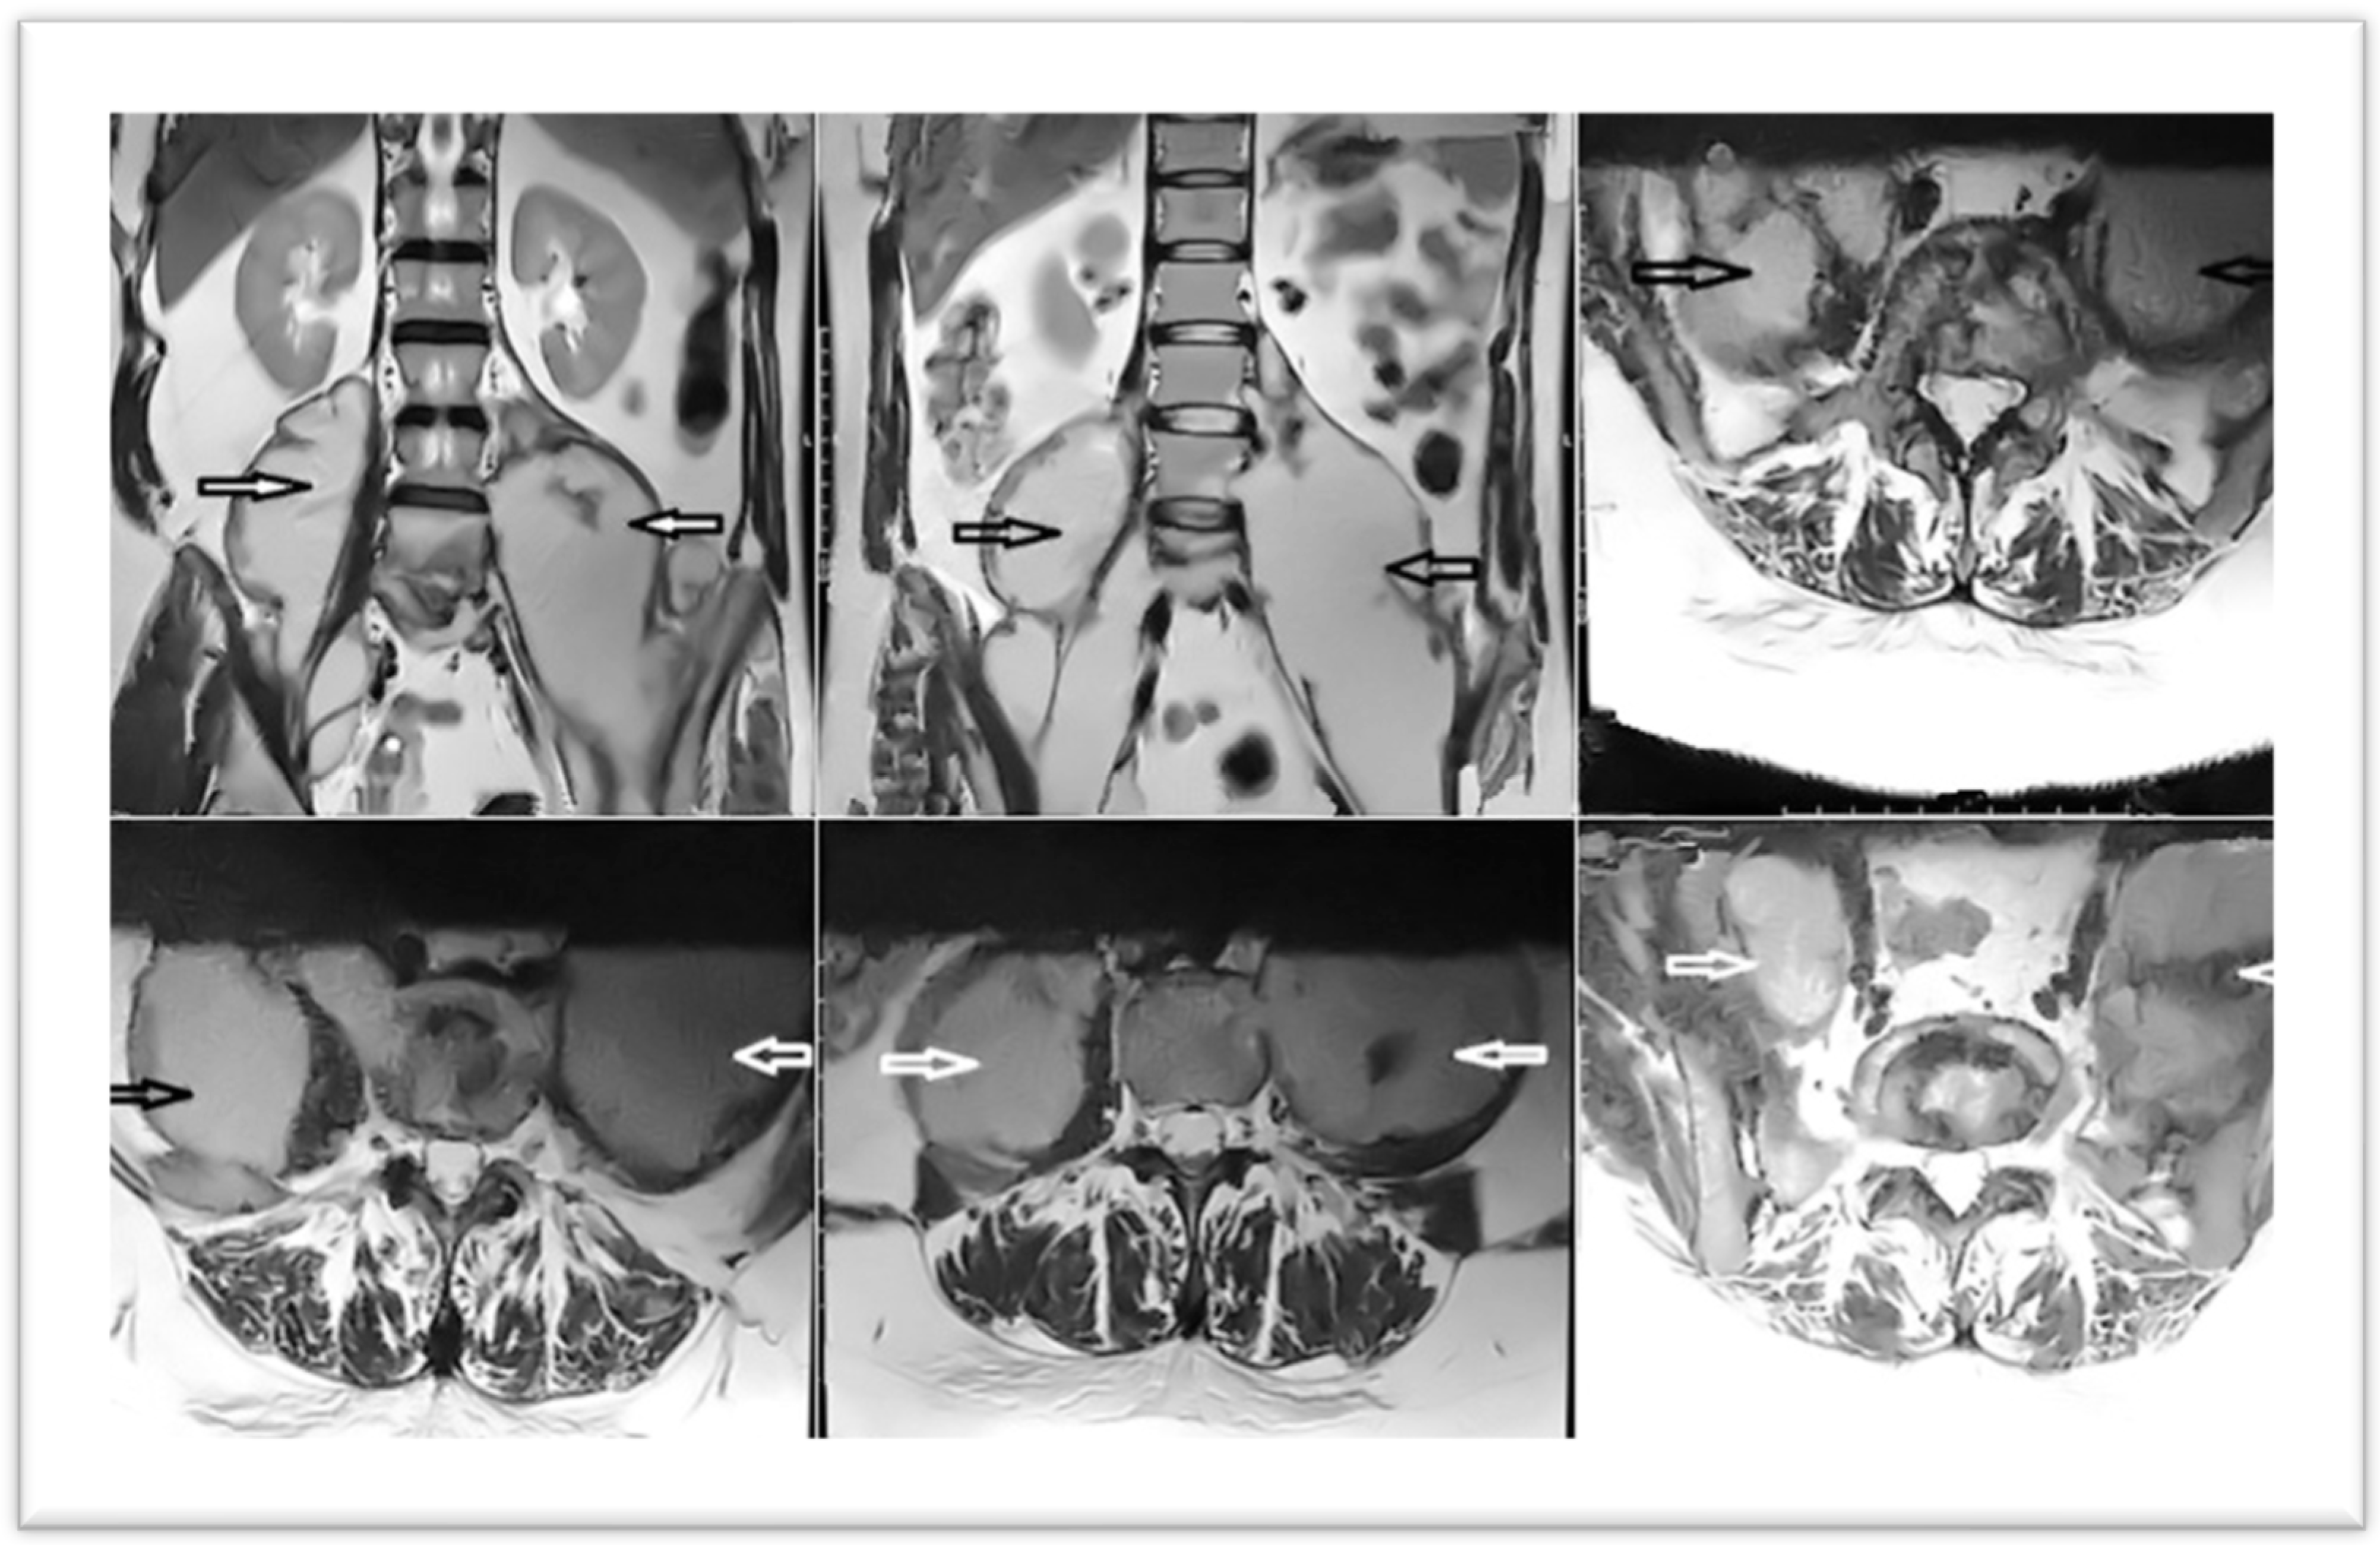

Two days postoperatively, a contrast-enhanced MRI revealed spondylodiscitis L4, L5, with L5 trans-somatic extension; small prevertebral collection; anterior epidural infection L4–S1; resolution of accumulations in the psoas major, regressive iliac abscess; and left coxofemoral osteoarthritis, characterized by pinching of the left coxofemoral joint space, with subchondral edema (Figure 5).

Figure 5. MRI aspect—two days postoperatively (arrows indicate resolution of abscesses under drainage).